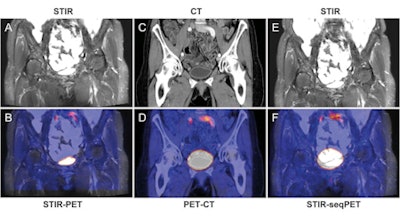

Simultaneous MR images included 3D T1-weighted fast low-angle shot (FLASH) and coronal T2-weighted short-tau inversion recovery (STIR) sequences in the abdomen. In the thoracic region, coronal STIR and coronal T1-weighted 3D gradient-echo sequences were conducted.

For the abdominal regions, regardless of the modality, the researchers found the greatest image misalignments in the bladder (mean, 9.6 mm ± 6.6), followed by the liver (mean, 9.0 mm ± 5.6) and the spleen (mean, 8.7 mm ± 5.4).

The mean image misalignment was 5.8 mm (± 2.8) for all organs in simultaneous PET/MRI, compared with 7.2 mm (± 5.1) for PET/CT and 11.9 mm (± 6.3) for MR images retrospectively fused with PET data from PET/CT.

The analysis of single organs showed no significant differences between STIR PET/MRI and PET/CT in the upper abdominal organs, although STIR PET/MRI showed the least misalignment in the liver, spleen, and right kidney.

The alignment of all upper abdominal organs was significantly better with STIR PET/MRI than with sequential STIR PET/CT. In the bladder, the alignment was significantly more accurate with STIR PET/MRI than with PET/CT and sequential STIR PET/CT.